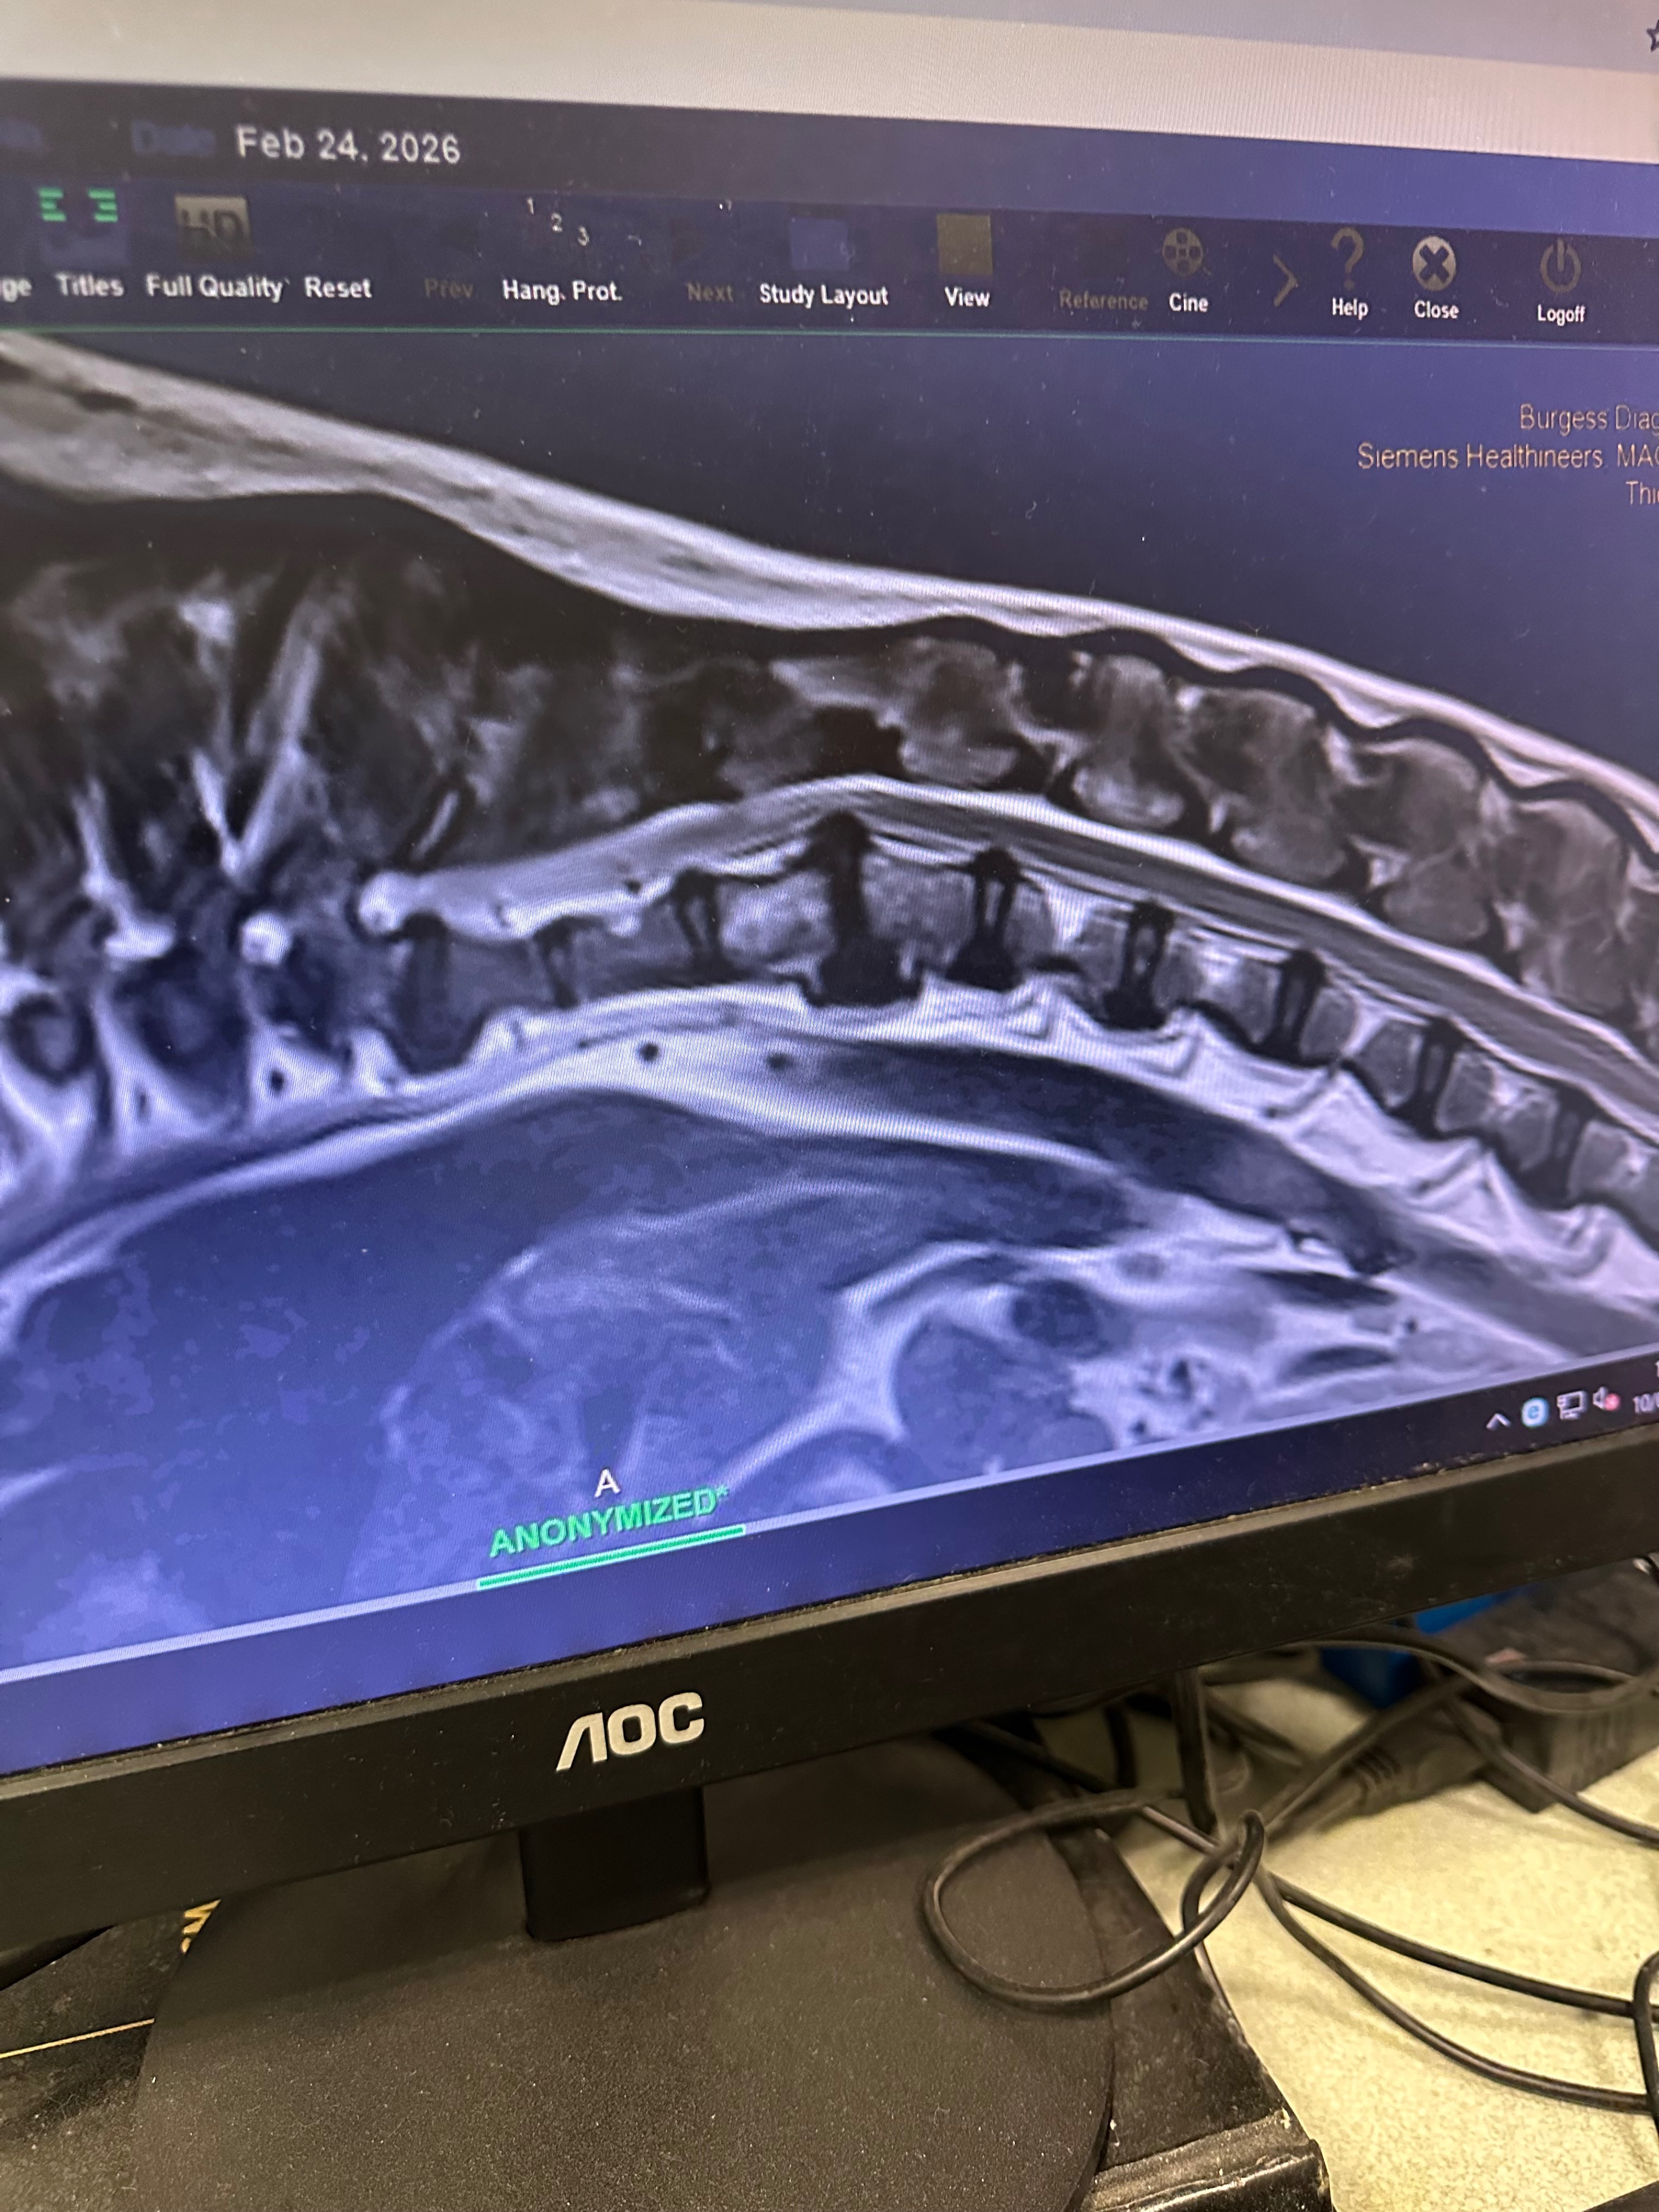

One of the major heath issues he’s dealing with is the horrendous Intervertebral Disc Disease (IVDD) on his spine.

At the beginning of this year, Arlos IVDD appeared near his neck and one of the discs burst, causing him a lot of pain and not being able to move properly. He then had an MRI, then urgently leading to surgery which he is now recovering from.

Upon our post-op check, the vet informed us of another complication on Arlos MRI scan: There is another disc in the middle of his back that is bulging and is a ticking time bomb from bursting, but this time it’s right on his spinal cord which could cause paralysis or worse.